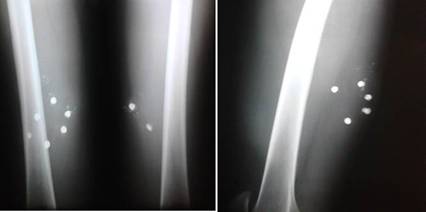

Los estudios radiográficos (Fig.1.) revelaron la presencia de 2 proyectiles en el muslo derecho y 6 en el izquierdo. La vista lateral muestra uno de estos proyectiles a una profundidad que se correspondía con la región anatómica del nervio ciático.

Se decidió intervenir quirúrgicamente con anestesia local, sedación y con la ayuda de un intensificador de imágenes. Se usó profilaxis antibiótica con cefazolina (2 g por vía endovenosa). Se logró extraer la totalidad de los proyectiles (Fig.2.) y el concentrador, que es la parte del cartucho que penetra en los tejidos a causa de los disparos a corta distancia.